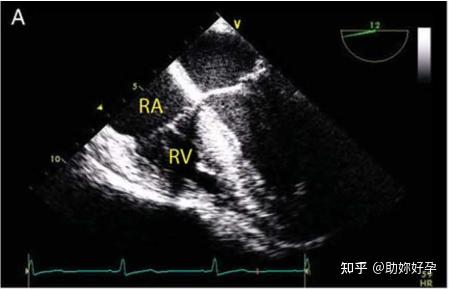

解剖结构以二维或三维的一系列帧显示在超声机的屏幕上。每一帧由形成扫描线的重复脉冲创建。根据焦点的数量,这些脉冲可以被复制(图 3A)。时间分辨率是从一帧开始到下一帧的时间,它代表了超声系统区分快速移动结构的瞬时事件的能力,例如,在心动周期中。可以通过以下方式提高帧频并提高时间分辨率: